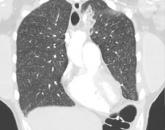

ArticleLung complications of prescription drug abuseAuthor:Josiah D. McCain, MDPublish date: December 3, 2018Opioid tables crushed, then injected intravenouslyRead More